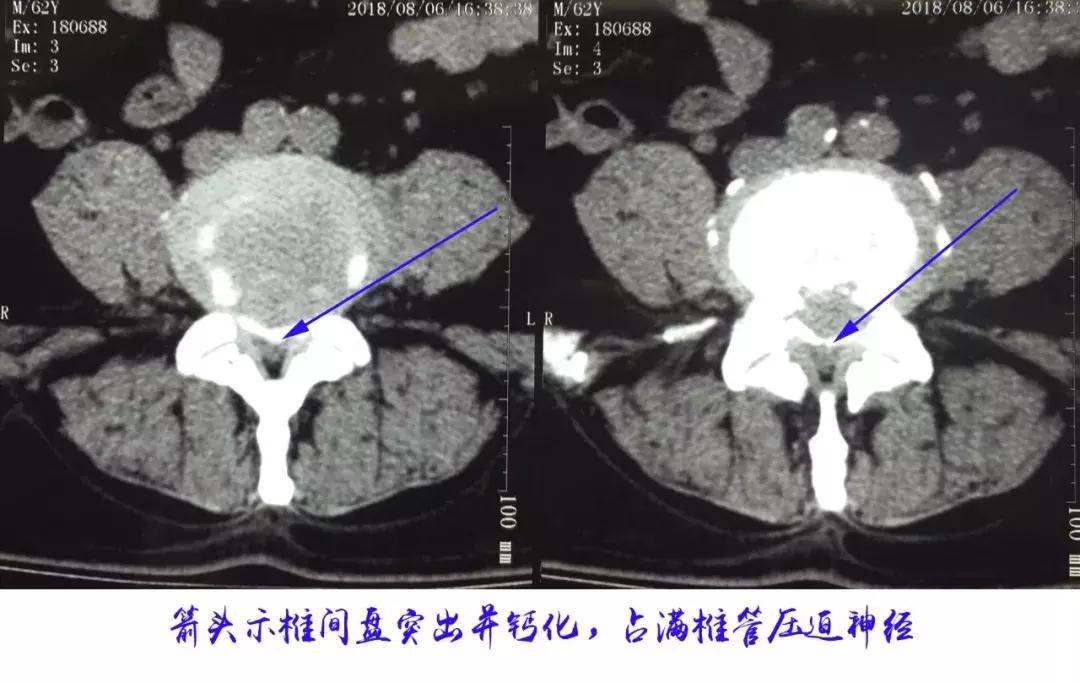

今年62岁的患者李某,多年来一直被腰腿疼痛困扰,腰背疼痛伴双下肢抽痛沉重,单次行走不足100米,就必须得蹲下来休息一会才能继续走几步,到医院就诊检查,诊断为腰椎间盘突出合并腰椎管狭窄症需要手术,李某因患有十余年的糖尿病病史,血管硬化,合并有高血压及冠心病,近两年先后发生过脑梗及心梗,并因此放了4枚心脏支架,面对这样的身体情况,多家医院均拒绝给老李实施手术。

李某饱受病痛折磨,辗转反复多方打听,得知西安市中心医院骨科开展的微创技术治疗腰椎间盘突出症创伤小恢复快,于是来到中心医院,骨科团队为其进行了详细的查体进一步明确了诊断,并深入细致地了解了患者的合并内科疾病情况,及时安排多学科会诊,调整内科疾病情况。2019年04月22日,郭华副院长及严少荣主任带领的骨科团队,用目前最先进的3D显微镜为患者实施了微创手术,取得了满意的效果。

郭华副院长介绍,得了腰椎间盘突出症并不可怕,我们有最先进的微创技术和设备,可以用更加微创的方式安全有效地给患者解除病痛:如果单纯的腰椎间盘突出症,我们可以局麻下用7mm切口进行椎间孔镜手术解除病痛;如果椎间盘突出合并椎间不稳或椎管狭窄需要融合,那我们可以便用3D显微镜辅助通道下微创手术,3D显微镜可以将术野放大并立体化,可以将葡萄大小的术区变成西瓜大小,让手术变得更清晰、更安全、更精细化,复杂手术也就变成了简单手术。科技造福人类,我们将用最先进的技术和设备为广大患者解除病痛。